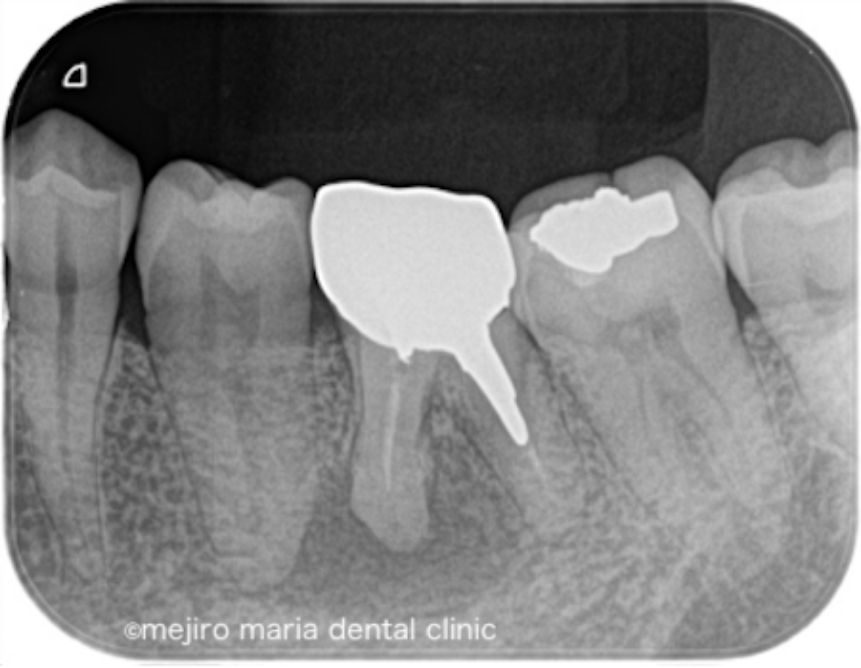

当院にて根管治療を開始するも根管治療の反応は乏しく、術前に確認できていた症状の改善は認められませんでした。その為、この患者様には歯根端切除術を追加で行い、マネージメントをさせていただくこととなりました。

歯根端切除術時に根尖を3mmほど切断したところ、根尖を取り囲むほどの歯石が確認され、この歯石の感染が根尖性歯周炎の治癒を妨げていた可能性がありました(写真)。